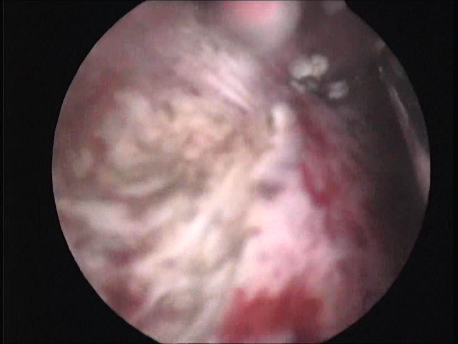

- Infertility and recurrent loss (Subfertility): Infertility means the inability to conceive and recurrent pregnancy loss means loss of 3 or more (in practice, usually 2 or more) consecutive early pregnancy (less than 5 months). Uterine pathology such as abnormal shape (septum or the T shaped uterus), submucous fibroids or polyps, and intrauterine adhesions can cause subfertility. Tubal block due to spasm or mucus plugs can contribute to infertility and can be opened by hysteroscopic cannulation.

- Abnormal uterine bleeding: Heavy, prolonged or irregular bleeding can be caused by submucous fibroids and polyps.

- Intrauterine foreign bodies: Missing copper T embedded in the uterine wall or retained fetal bones or pregnancy following a miscarriage can contribute to irregular bleeding, infection or subfertility.